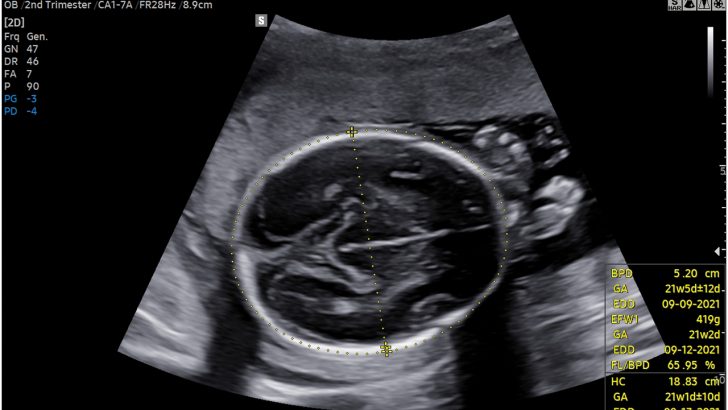

‘Biometry Solution’ recognizes images such as the fetal head, abdomen, lower extremities and others and measures the fetal growth and development while the ‘Fetal Heart Solution’ recognizes the view of the fetal heart, annotates the images and measures the necessary fetal heart structures for a thorough fetal heart anomaly assessments.

The image delineates that the fetal head is automatically recognized and measured along with the fetal growth when ‘Biometry Solution’ is executed.